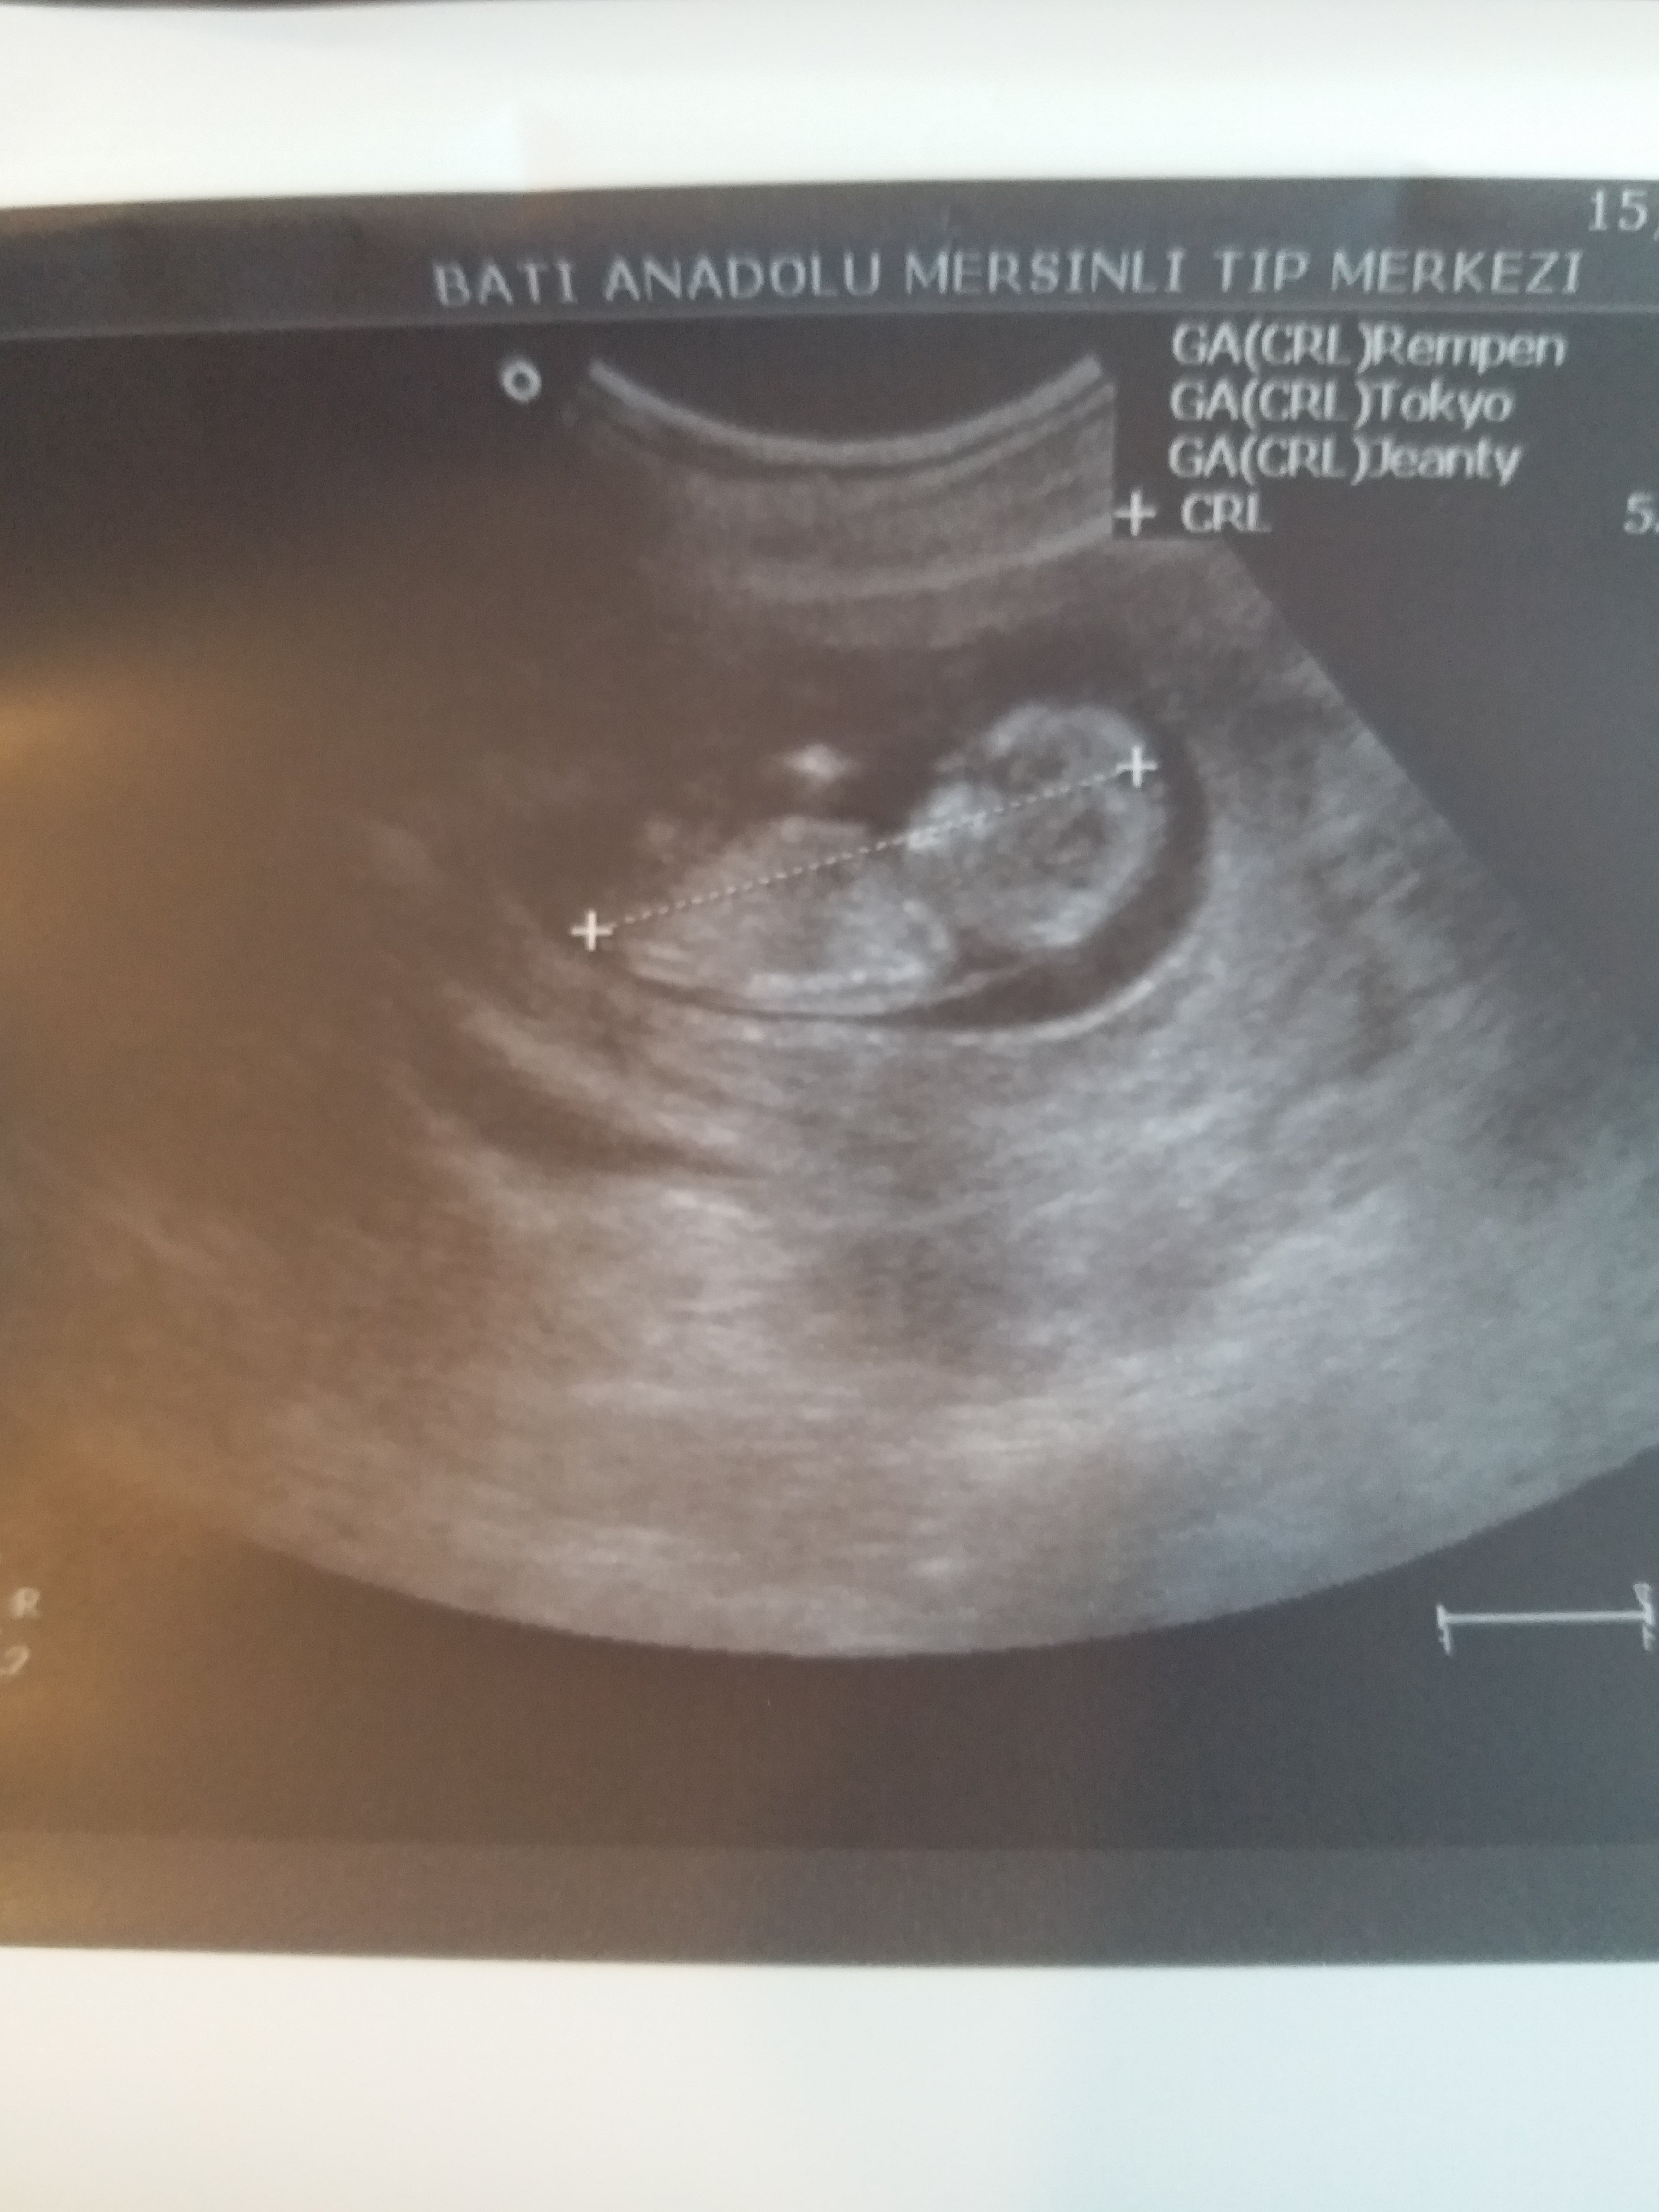

Banada yorum yapabilirmisiniz

Merhaba, emin olmamakla birlikte bebeğinizin cinsiyetinin erkek olduğunu düşünüyorum. Bebeğinizin cinsiyetini net olarak 16-17 - 20 haftalarda izlenebilir.